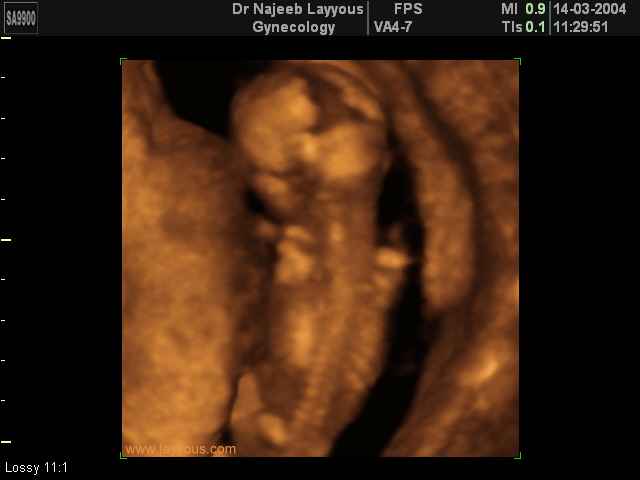

- Fetal Behavior Ultrasound Photos

Ultrasound Photos in 3D showing Fetal Behavior Inside the uterus | Dr N Layyous